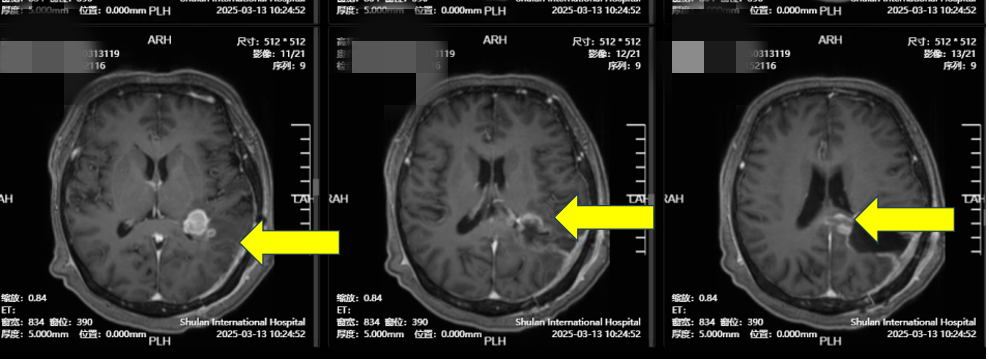

2月初,高女士因记忆力下降,思维迟缓和四肢无力就诊于山东某知名三甲大医院。进行PET-CT+颅脑MRT检查,提示“左顶叶、胼胝体占位性病变”。一场紧急手术切除了肿瘤,但术后病理报告却让其家属心中一沉——“胶质母细胞瘤”,这是恶性程度最高、侵袭性最强的脑肿瘤之一。

(图1:术前:左顶)

(图2:术前:左顶+胼胝体)